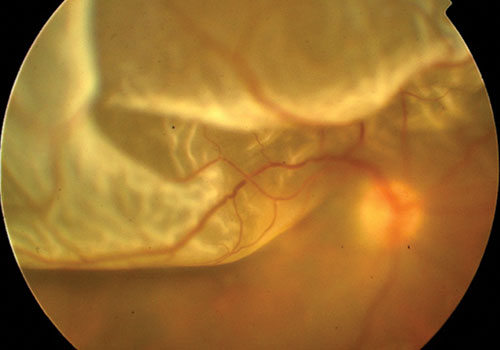

Il distacco di retina è una delle più gravi patologie che intessano la vista e l’occhio.

È la separazione della retina dal tessuto sottostante, la coroide.

Il paziente può percepire l’improvvisa comparsa di lampi luminosi (fosfeni), corpi mobili vitreali (miodesopsie), appannamento del campo visivo con la sensazione di una tenda che offusca la visione. Questi sintomi non indicano necessariamente un distacco di retina ma possono essere sintomi premonitori e quindi va contattato immediatamente il proprio oculista.